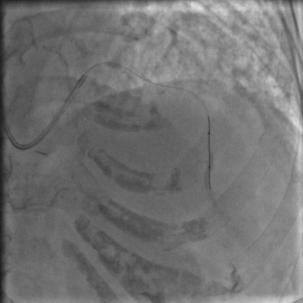

按照常规,更换指引导管,送入导丝,顺利通过闭塞病变到达前降支远端,很顺利,D-to-B时间70分钟,达标,曙光在前头。

图5

导丝过了之后常规造个影:

图6

没通,这个也很正常,急性冠脉闭塞导丝过了之后血栓还堵着是很经常的事,按常规打点欣维宁,考虑到她86岁,打入8ml欣维宁,造影: